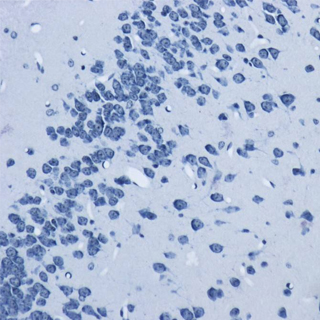

首頁 > 產品分類 > 實驗技術服務 > 病理學實驗